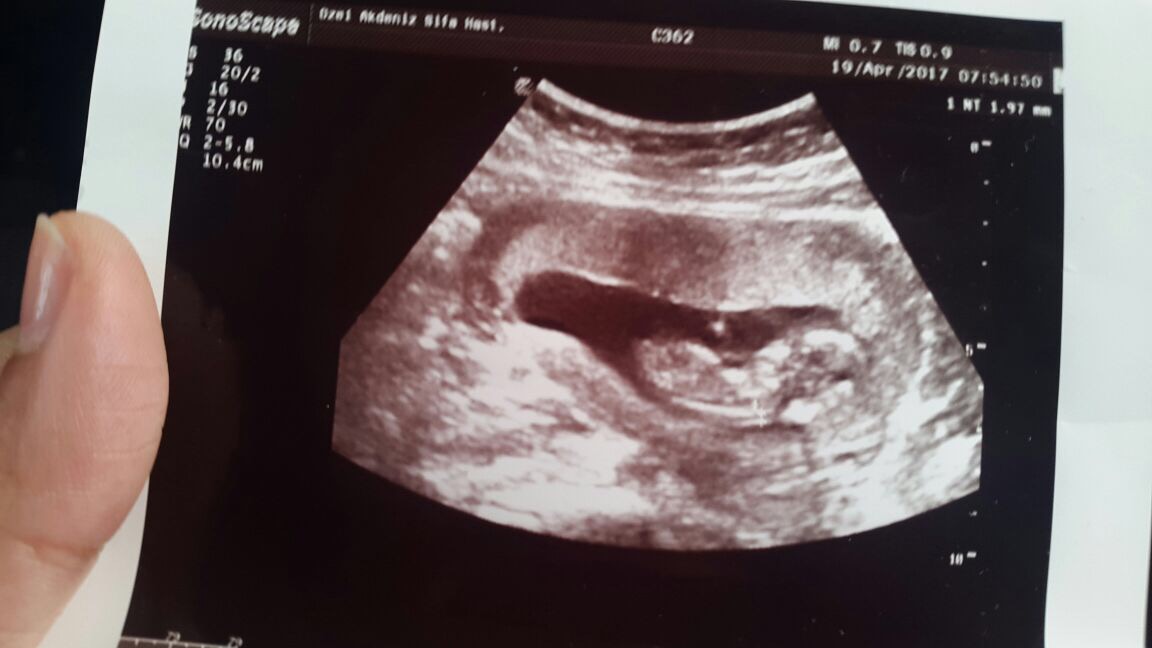

Bagdat1987 Yeni Üye Üye 21 Nisan 2017 #238 Benimki de bu 🙂 inşallah kısa süre de görürsünüz mesajımı 12+3 haftalık Ekli dosyalar IMG_0120.JPG 94,2 KB · Görüntüleme: 879